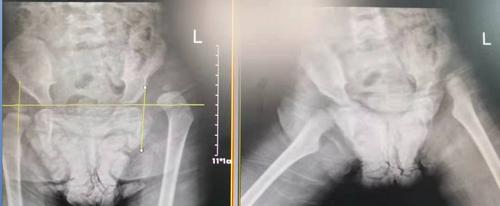

术前

据了解,玥玥的左腿比右腿要短3厘米,导致她走起路来“不对头”:一拐一拐的,像小鸭子走路一样。